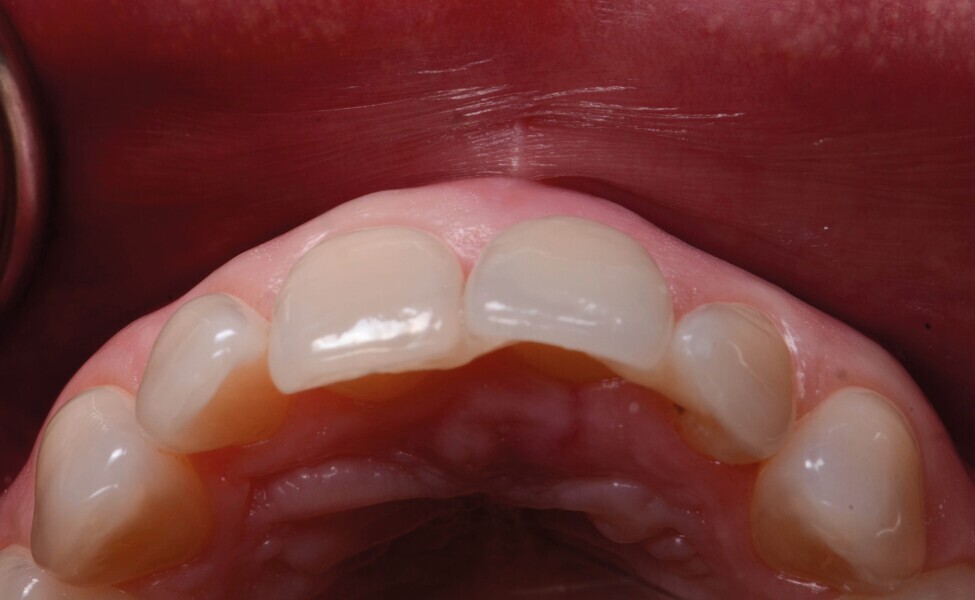

Une patiente de 42 ans est adressée au cabinet pour le remplacement de son incisive centrale supérieure gauche (dent 21) qui est à l’origine de douleurs. Un antécédent de traumatisme dentaire remontant à l’adolescence est rapporté. La ligne du sourire de la patiente est normale, mais la dent 21 est égressée (Fig. 1) La gencive présente un biotype raisonnablement épais et le feston gingival est très marque.

Fig. 2a : Vue préopératoire intraorale